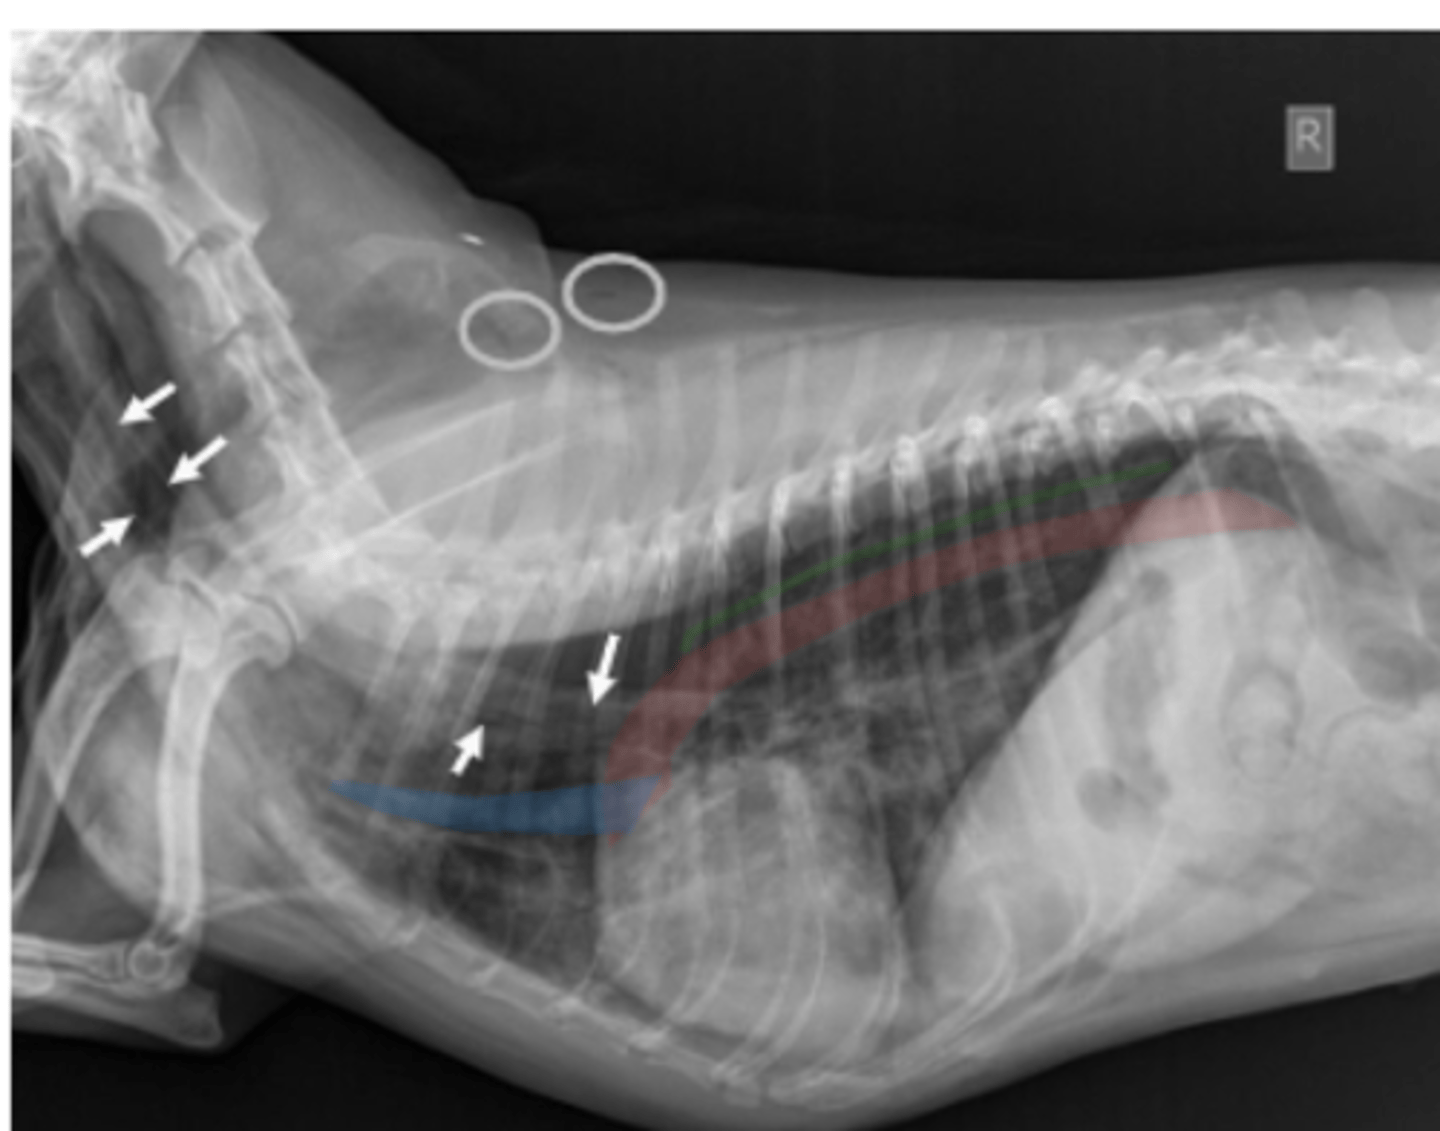

megaesófago

patología:

megaesófago, por cuerpo extraño

neumonía por aspiración por

la parenquíma pulmonar, por riesgo de neumonía por aspiración

si vemos megaesófago en una radiografía, es importante evaluar: